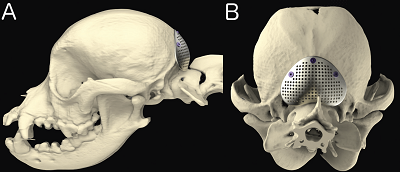

Foramen Magnum Decompression with Free Autogenous Adipose Tissue Graft for Treatment of Caudal Occipital Malformation Syndrome in Dogs. Erin Y. Akin, Nora H. Ortinau, Andy Shores, M. B. Carnes, Jill Narak. 2009 ACVS Vet. Symposium Abstract. Quote: "The objective of this study was to describe and evaluate a modified surgical technique using foramen magnum decompression (FMD), durotomy, duroplasty with swine intestinal submucosa (SIS), and a free autogenous adipose tissue graft (FAATG) for the treatment of canine caudal occipital malformation syndrome (COMS). Fourteen client-owned dogs with MRI evidence of COMS and surgical treatment with FMD were included in this 18-month prospective study (10/07 - 3/09). Breeds treated included Cavalier King Charles Spaniel (11), Chihuahua (2), and Pomeranian (1). Surgical decompression of the foramen magnum and durotomy were performed in a fashion similar to previously described techniques. ... The dura was marsupialized, suturing it to the surrounding fascia using simple interrupted sutures of 5-0 polydioxanone (fig 3). The SIS was sutured to the dura in a tent-like fashion using simple interrupted sutures of 5-0 polydioxanone. The FAATG, typically obtained from the gluteal region, was placed over the defect followed by a sheet of gelatin foam. ... Overall, recovery was considered to be good to excellent by owners. To date, none of the patients that have undergone this surgical procedure have required further surgical intervention due to postoperative compressive scar formation that has been reported in the previous literature. ... In dogs that require FMD in the treatment of COMS, this modified technique using a FAATG should be considered. Current clinical outcomes of patients that were treated for COMS using this technique showed excellent results similar to current published literature without intraoperative complications and clinical improvement with a decrease in clinical signs postoperatively. The use of the titanium mesh, placement of the screws, and the exothermic reaction of the overlying methyl methacrylate may contribute to tissue trauma. The authors conclude that with the results of this study, this procedure is clinically effective and the use of a titanium mesh, additional hardware and methyl methacrylate offers no advantage in canine COMS patients."